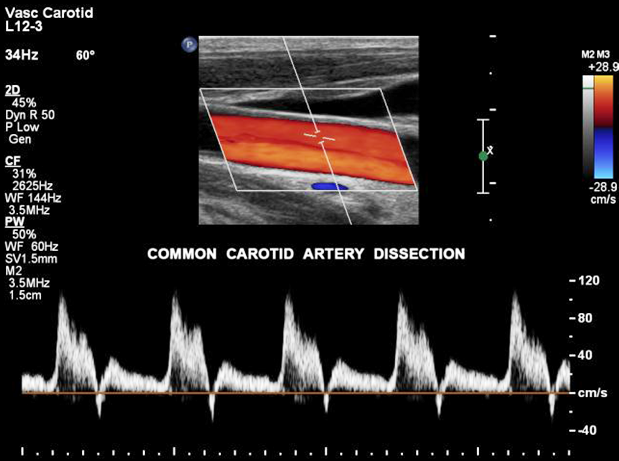

A carotid ultrasound is performed to test for narrowed carotid arteries. Narrowed arteries increase the risk of stroke.

Carotid arteries may be narrowed due to plaques which are made up of fat, cholesterol, calcium and other substances.

Early diagnosis and treatment of a narrowed carotid artery can reduce chances of a stroke.

Carotid ultrasound is recommended if you have transient ischemic attacks (TIAs) of any symptoms suggestive of narrowing od the carotid arteries.